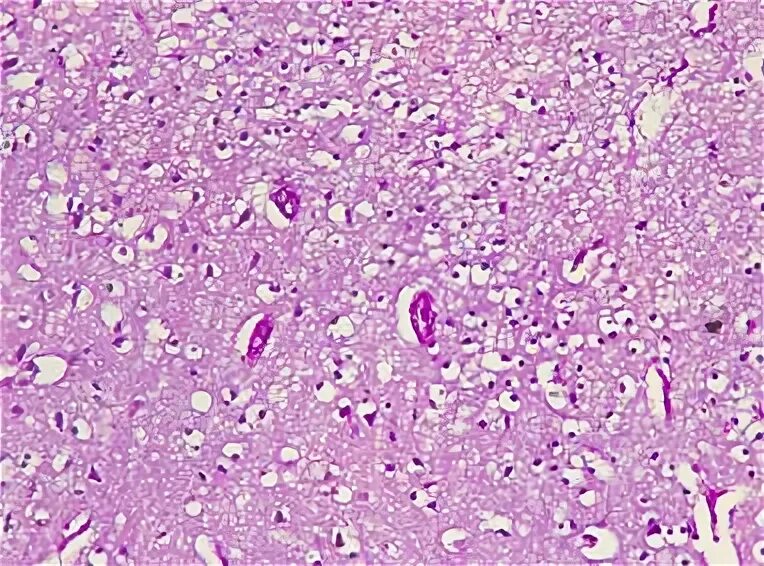

Смешанный периваскулярный инфильтрат при крапивнице